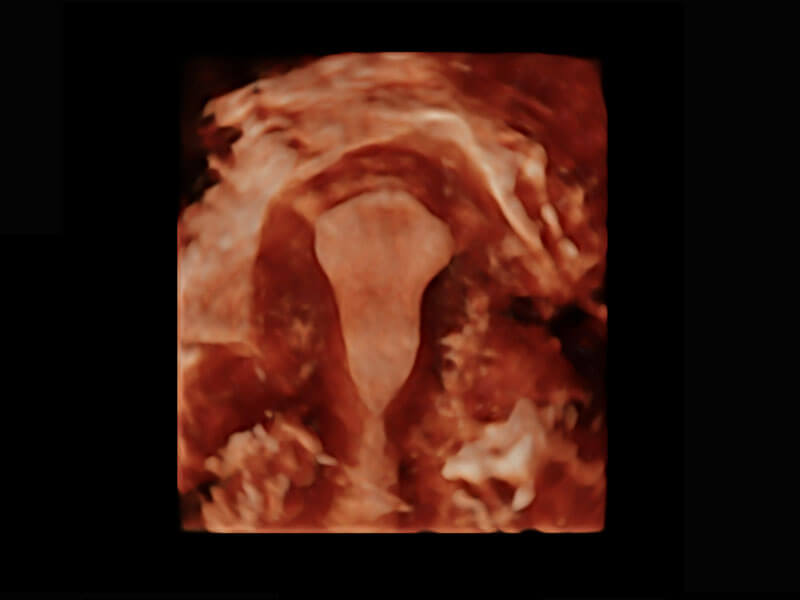

腔内三维-宫内节育器

腔内三维-光影成像

P60为盆底超声检查提供应用方案,多种腔内及腹部容积探头提供从二维、三维到四维的优异图像品质,实时快速三维容积数据获取,专业的测量工具包等人性化设计,为超声医生诊断提供有力保障。

Lev.Hiat A-r: 16.33 cm2

Lev.Hiat H-r: 53.70 mm

Lev.Hiat W-r: 43.96 mm

Lt-LUG-r: 24.16 mm

Rt-LUG-r: 19.94 mm

能够简化盆底检查的操作流程,可在二维模式及三维成像模式下实现一键自动提取出标准切面、自动识别当前切面、自动测量,提升盆底检查的高效性,同时也能让青年医生快捷的获得准确的检查结果。